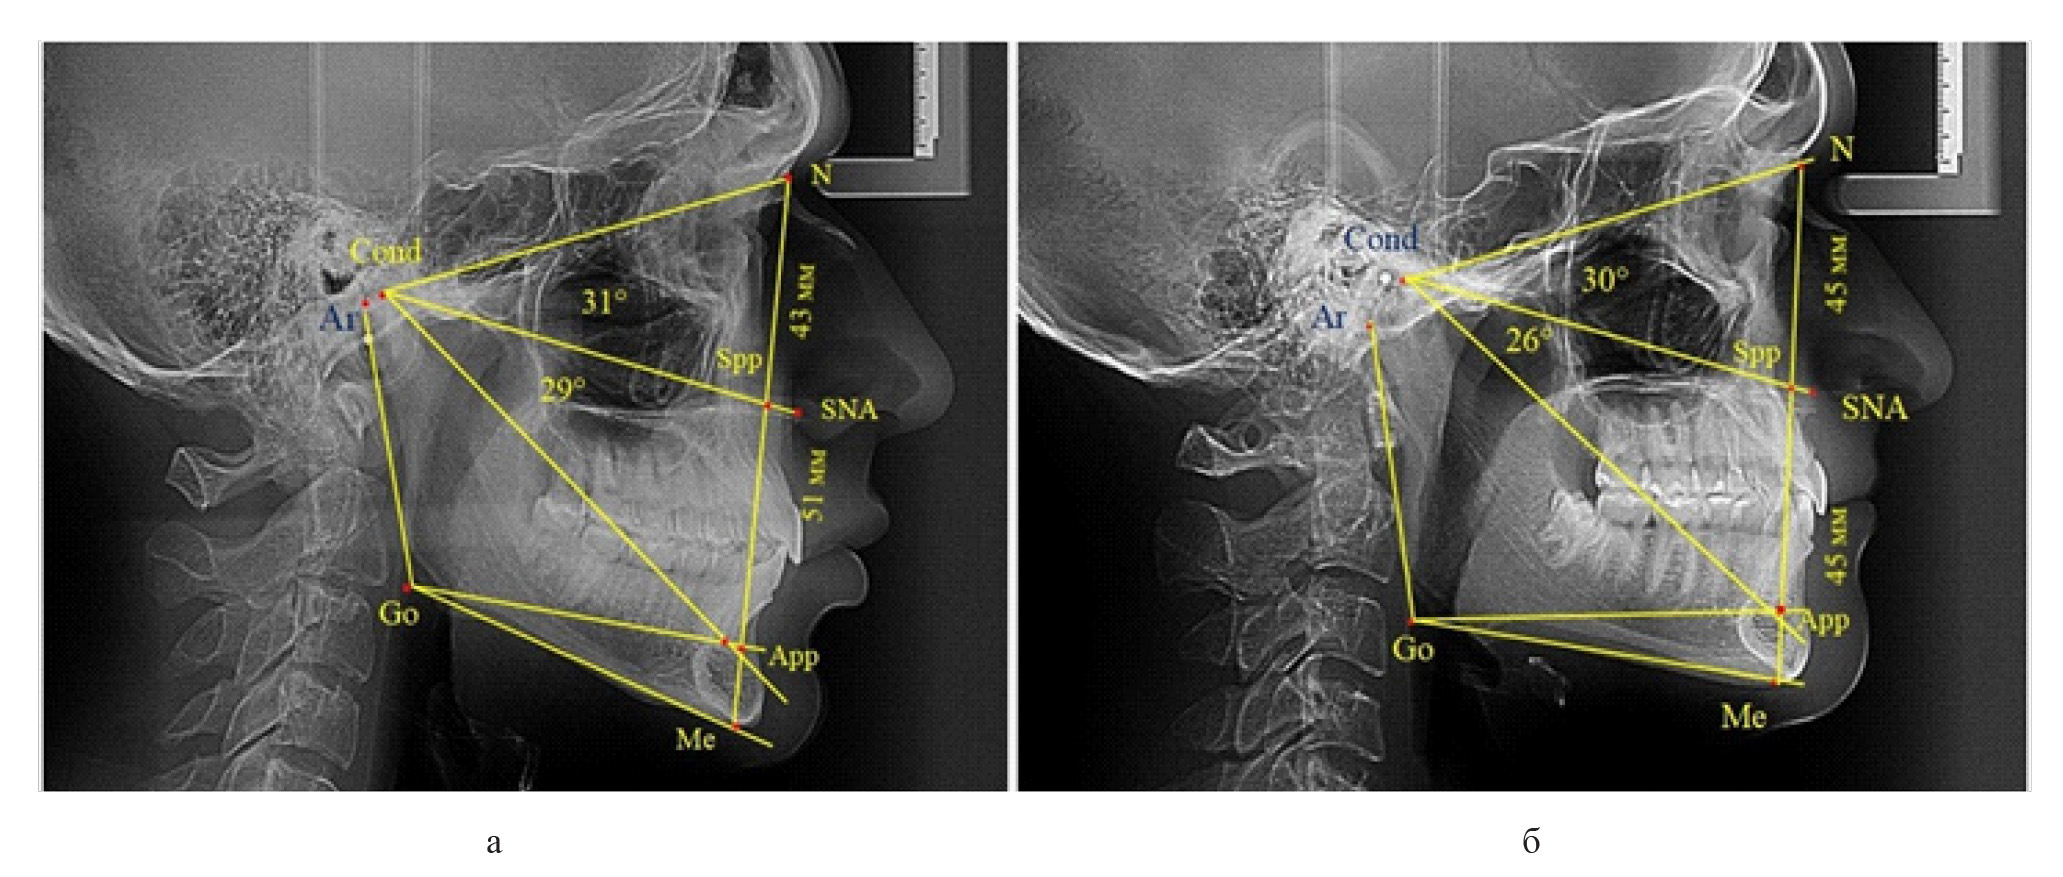

Вертикальная линия передней высоты лица (N-Me), после ее пересечения с линией Cond-SNA, определяла положение точки Spp, при этом вертикаль N-Spp использовалась в качестве оценки высоты назального отдела лица. Продолжение линии Go-Api до пересечения с линией N-Me позволяла определить положение конструктивной точки Арр и оценить линейные размеры гнатической части лица по величине вертикали Spp-Арр (рис. 1).

Рис. 1. Методы оценки основных параметров ТРГ для определения вертикальных размеров лицевого отдела головы

Среди пациентов с аномалиями челюстно-лицевой области в вертикальном направлении у 24 человек определялась глубокая резцовая окклюзия/дизокклюзия (рис. 5).

Рис. 5. Варианты ТРГ с оптимальными размерами носового отдела и оптимальными (а) и укороченными (б) размерами гнатической части лица

При этом только в двух случаях [(8,33 ± 5,64) %], параметры носового и гнатического отдела соответствовали норме. У 9 человек [(37,59 ± 9,88) %], при оптимальных параметрах назального отдела отмечалось уменьшение высоты гнатического отдела, вплоть до патологических показателей.

У людей с глубокой резцовой окклюзией нередко отмечалось изменение параметров носового отдела лица. Так, в 7 случаях было выявлено снижение параметров как носового, так и гнатического отделов лица. У 5 человек [(20,83 ± 8,28) %], отмечалось уменьшение носового отдела лица при оптимальных параметрах гнатического отдела.

В одном случае [(4,17 ± 4,08) %], определялось патологическое увеличение назального отдела лица при уменьшении гнатической его части. Некоторые варианты ТРГ пациентов с глубокой резцовой окклюзией представлены на рис. 6.

Рис. 6. Варианты ТРГ с уменьшенными размерами носового отдела и оптимальными (а) и укороченными (б) размерами гнатической части лица при глубокой резцовой окклюзии